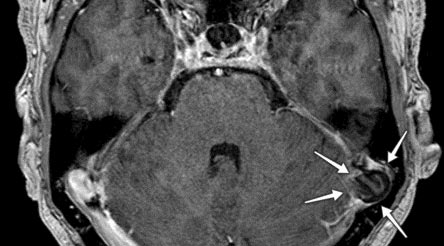

Specialeansvarlig overlæge Søren Larsen underviste yngre ortopædkirurger i store håndskader og replantation